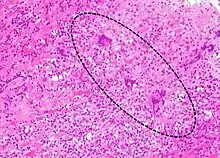

| A microscope image of myocarditis at autopsy in a person with acute onset of heart failure | |

The gold standard is the biopsy of the myocardium, in general done in the setting of angiography. A small tissue sample of the endocardium and myocardium is taken and investigated. The cause of the myocarditis can be only identified by a biopsy. Endomyocardial biopsy samples are assessed for histopathology (how the tissue looks like under the microscope): myocardial interstitium may show abundant edema and inflammatory infiltrate, rich in lymphocytes and macrophages. Focal destruction of myocytes explains the myocardial pump failure.[10] In addition samples may be assessed with immunohistochemistry to determine which types of immune cells are involved in the reaction and how they are distributed. Furthermore, PCR and/or RT-PCR may be performed to identify particular viruses. Finally, further diagnostic methods like microRNA assays and gene-expression profile may be performed.